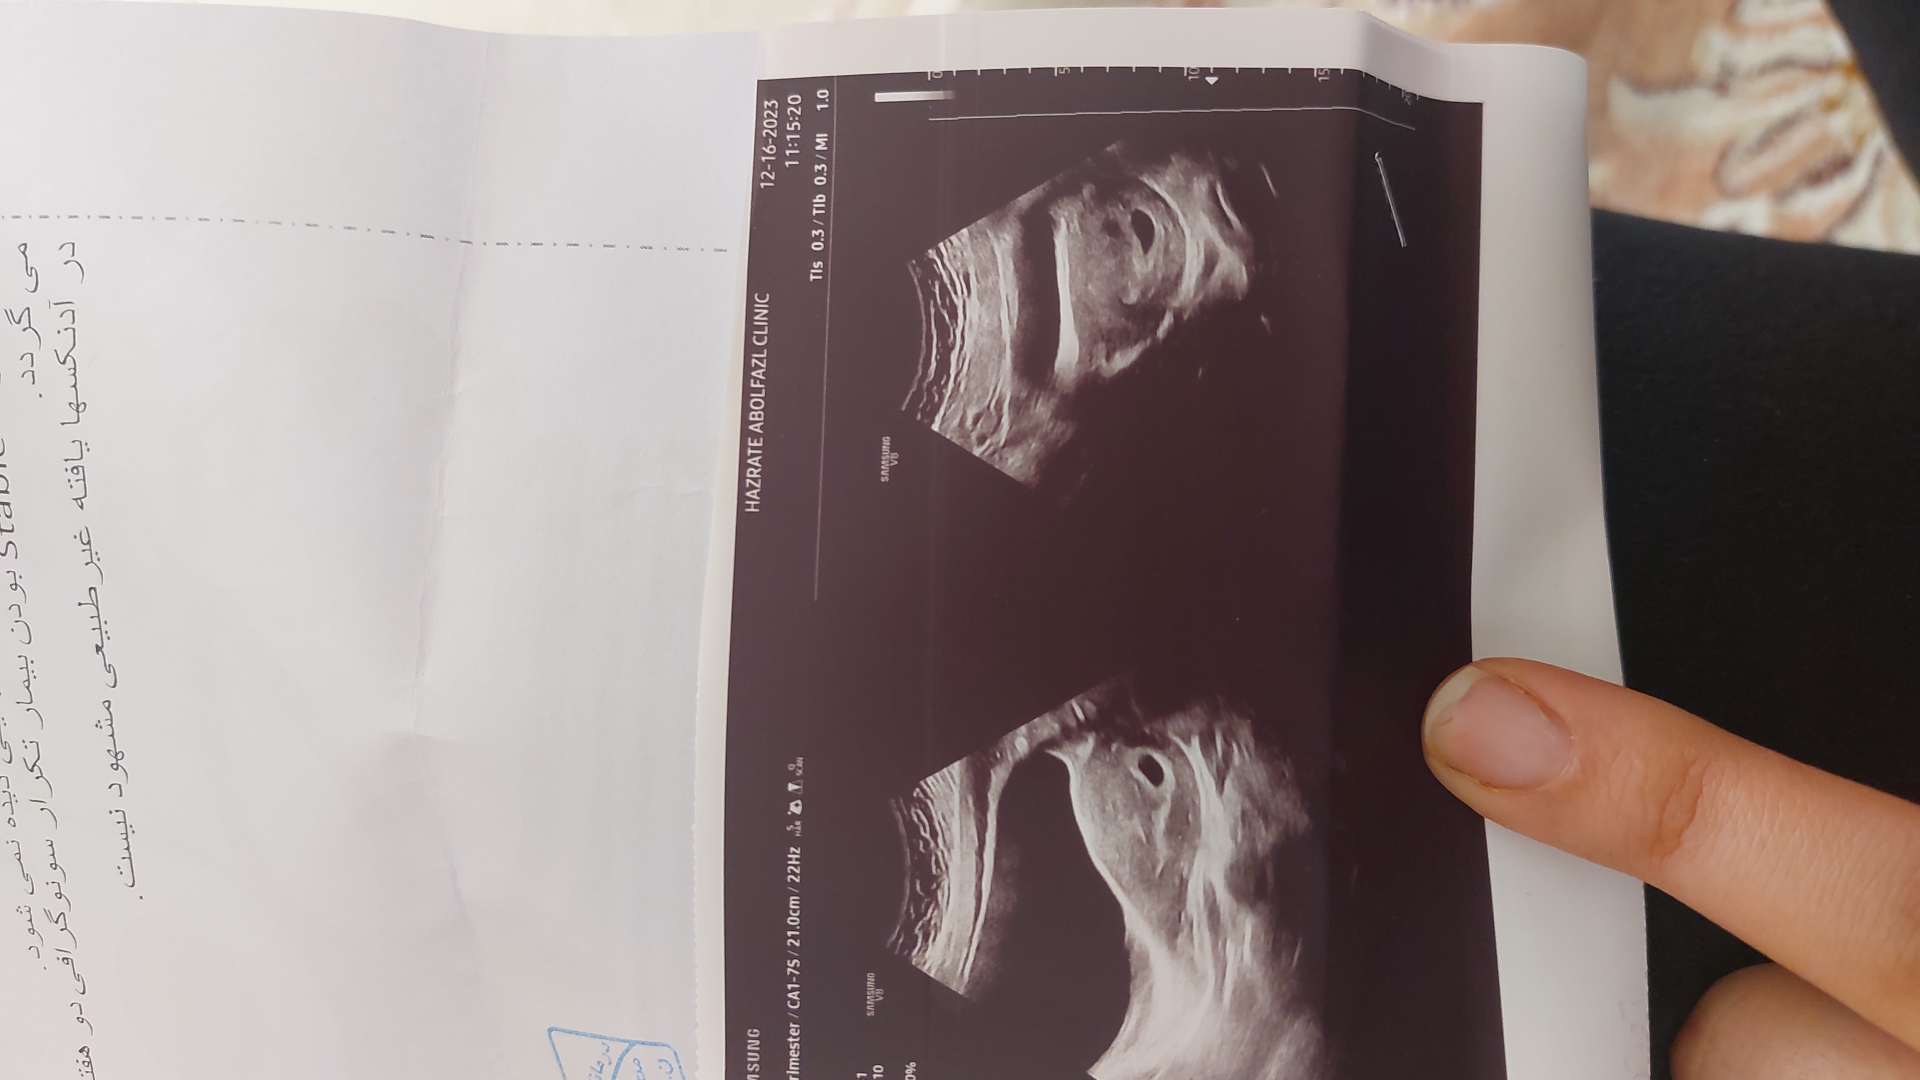

سلام دیروز رفتم سونو ۶ هفته و ۳ روز بودم طبق پریود .ساک حاملگی بود ولی گفت ضربان تشکیل نشده .

پارسالم قلب تشکیل نشد و سقط کردم .

دکتر گفت دو هفته دیگه برو دوباره